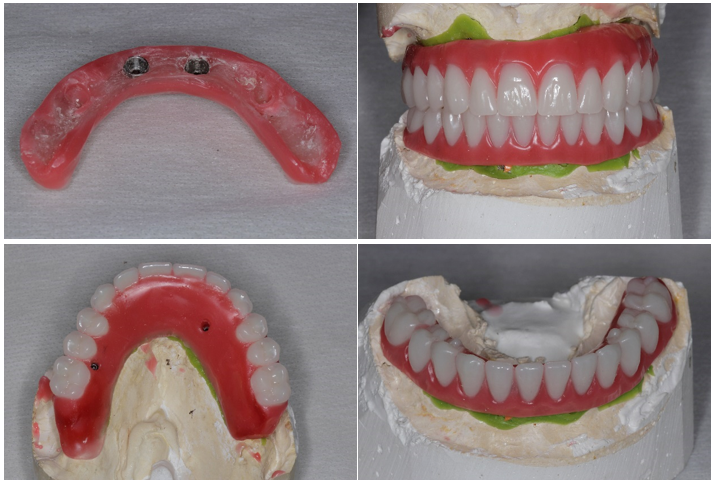

Abaixo a descrição das etapas de confecção das próteses protocolos superior e inferior:

1- seleção dos pilares intermediários (mini-cônicos), instalação e moldagem de transferência. Obtenção dos modelos de trabalho e confecção de base de prova e planos de cera com o uso de dois componentes (cilindros de metal para provisório do pilares mini-cônicos);

2- orientação dos planos de cera sobre as bases de prova (orientar suporte de lábio, altura incisal em repouso e no sorriso forçado, orientar plano de Camper e linha bipupilar, corredor bucal, dimensão vertical de repouso, de oclusão) para registro maxilo-mandibular. Seleção dos dentes e montagem dos dentes em laboratório;

3- prova da montagem dos dentes em cera – prova funcional. Aferição da estética e da função mastigatória. Envio ao laboratório para confecção do enceramento, fundição e acabamento/polimento da barra metálica;

4- prova e ajustes da barra metálica na boca do paciente;

5- prova dos dentes montados sobre a barra metálica;

6- instalação e ajustes das próteses.